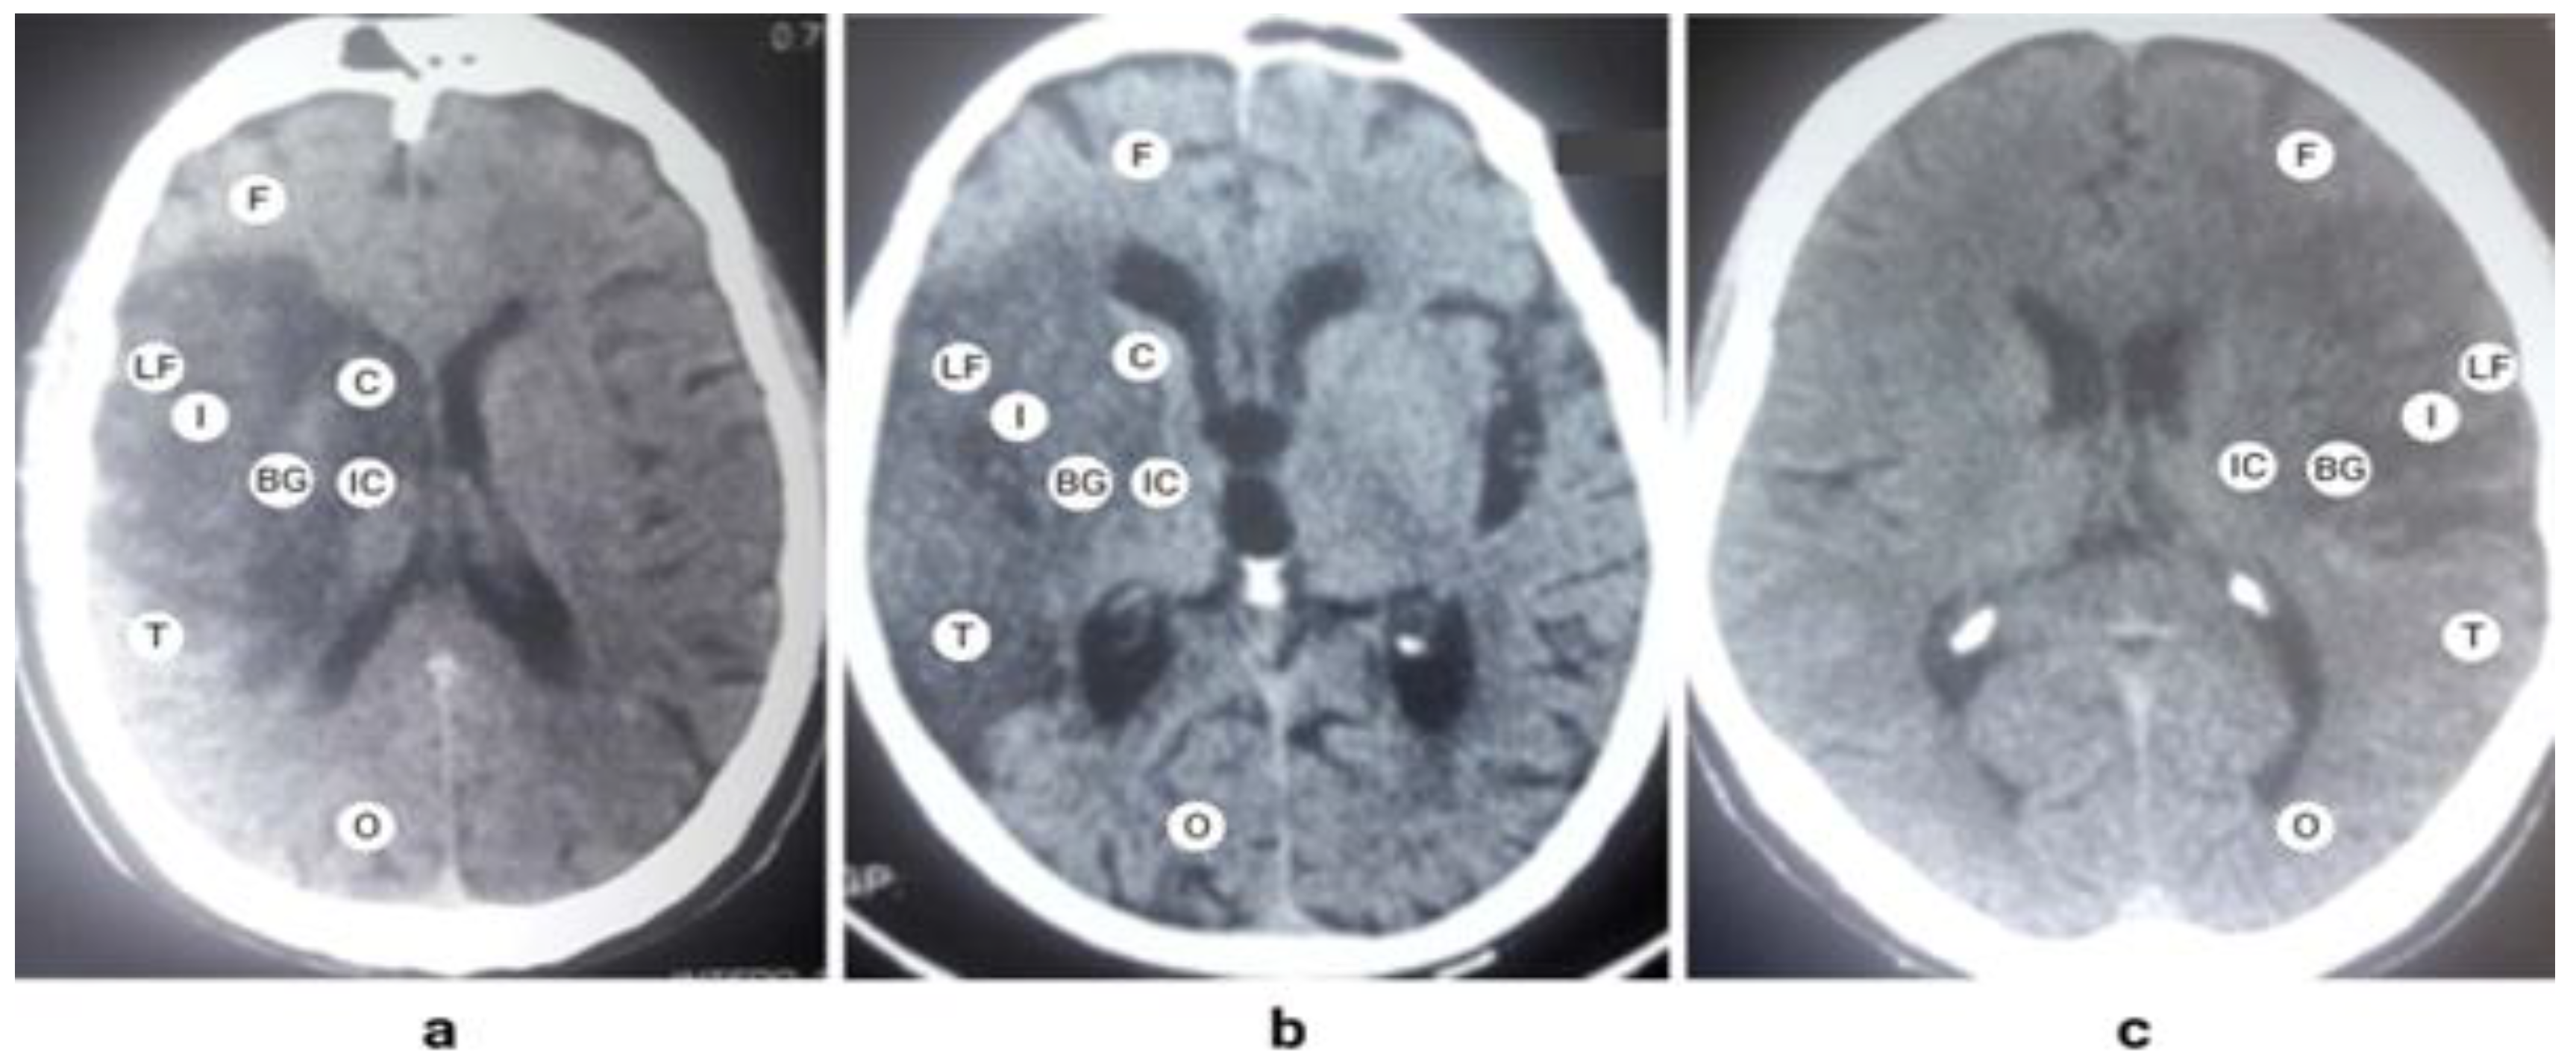

The neurovascular territory of the middle cerebral artery (MCA) is the central two-thirds of a hemisphere. Middle cerebral artery is a continuation of the intracranial part of the internal carotid artery. It is divided into five segments, M1 to M5, where M1 and M2 are denoted as large segments of MCA [12]. These large segments give penetrating branches to the ipsilateral basal ganglia, internal capsule and the deep white matter of the hemisphere. The anatomical course and the territory of MCA are shown in Figure 1. Being the main part, M1 segment’s occlusion produces a major infarction by limiting blood supply to a large part of the hemisphere. A characteristic pattern formed by the proximal occlusion of the MCA is a confluent signal of infarction involving the internal capsule, basal ganglia, and the insula, as shown in Figure 2. It extends to all lobes of the brain except the occipital lobe.

Figure 2. Axial views of brain computed tomography (CT) scans showing large infarctions due to proximal occlusion of the middle cerebral artery (MCA). Fig 2(a) and 2(b) depict infarct pattern for the right MCA, while Figure 2(c) illustrates the corresponding pattern for the left MCA. The characteristic sign of proximal occlusion of MCA on brain CT is a confluent signal of infarction that involves the internal capsule, basal ganglia and the insula. Internal capsule (IC), Basal ganglia (BG), Insula (I), Lateral fissure (LF), Caudate (C), Frontal lobe (F), Temporal lobe (T), Occipital lobe (O).